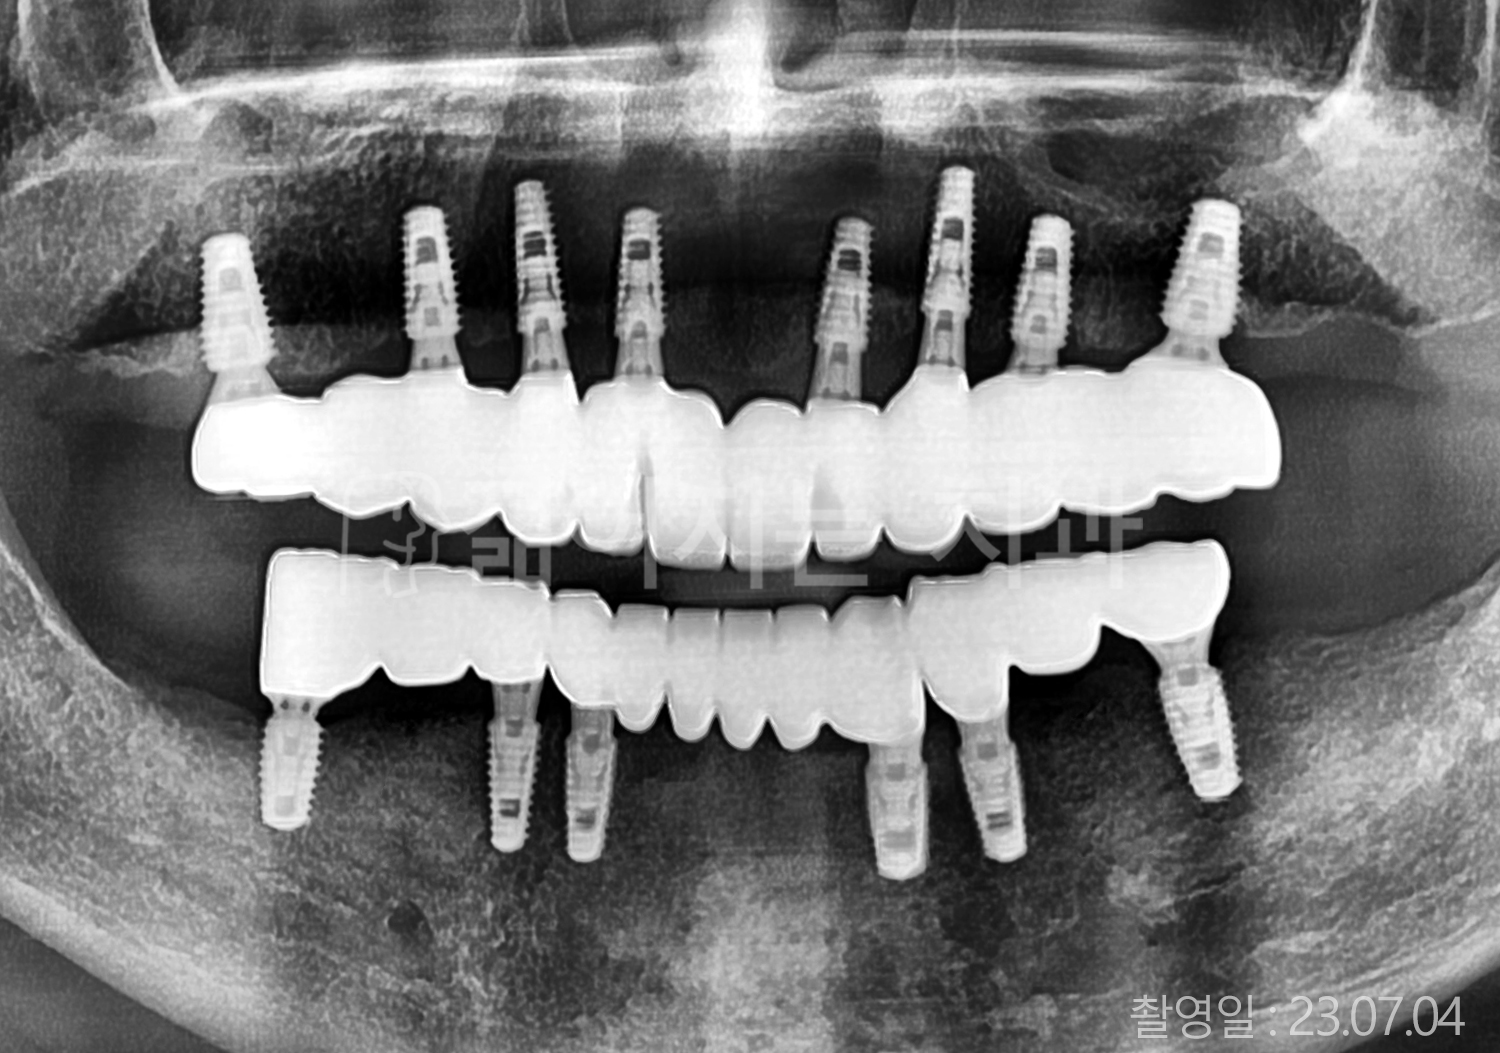

• 50대 고혈압, 당뇨, 고지혈증 전체치아 10개 이상 임플란트

• 60대 골다골증, 간경화 전체치아 10개 이상 임플란트

• 60대 고혈압, 고지혈증 전체치아 10개 이상 임플란트

• 50대 고혈압, 당뇨 전체치아 10개 이상 임플란트